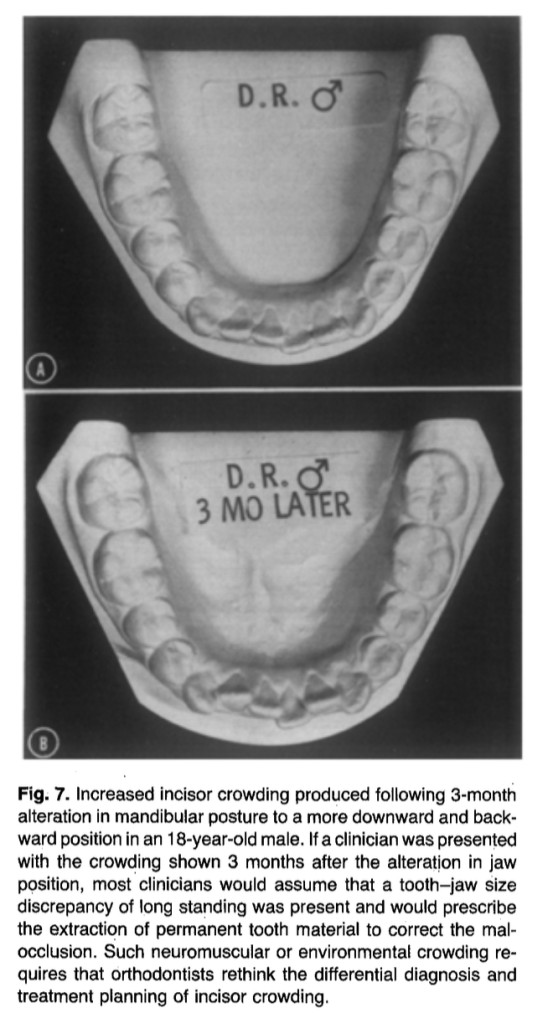

2️⃣ Incisor Crowding May Be Environmental

After adenoidectomy:

- Incisors often change from retroclined → proclined

- Arch circumference may increase

- Some crowding may resolve without extractions

📌 Not all crowding = tooth–jaw size discrepancy